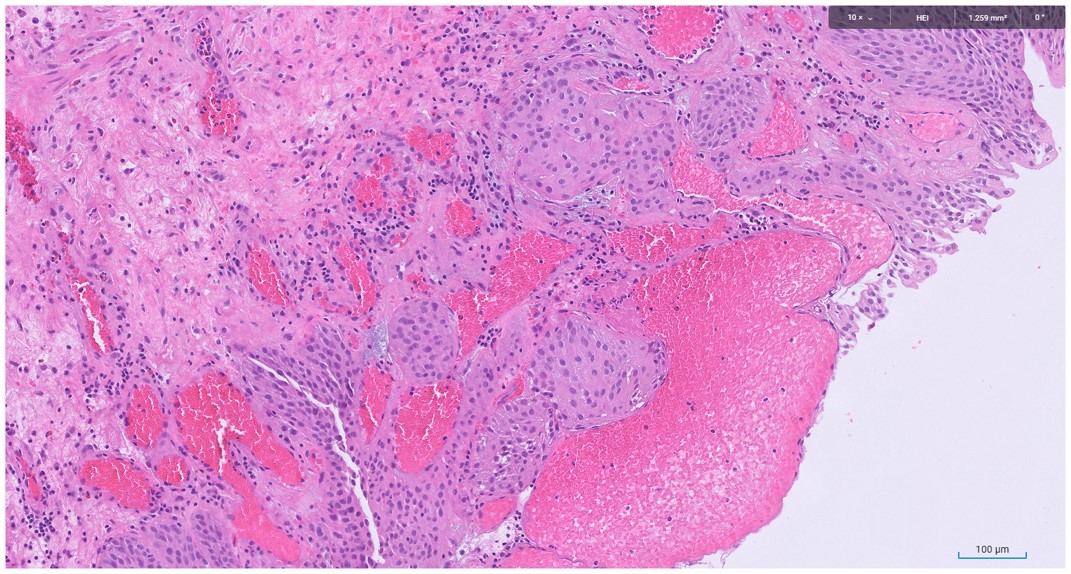

Microscopic image possibly detecting cancerous areas in human tissue

What is the most likely diagnosis?

1. Radiation cystitis

2. Cystitis cystica

3. Invasive urothelial carcinoma

4. carcinoma in situ

Radiation cystitis